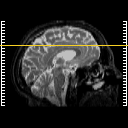

Click on sagittal image to select slice. Click on thin tickmark to change timepoint, or thick tickmark for overlay.